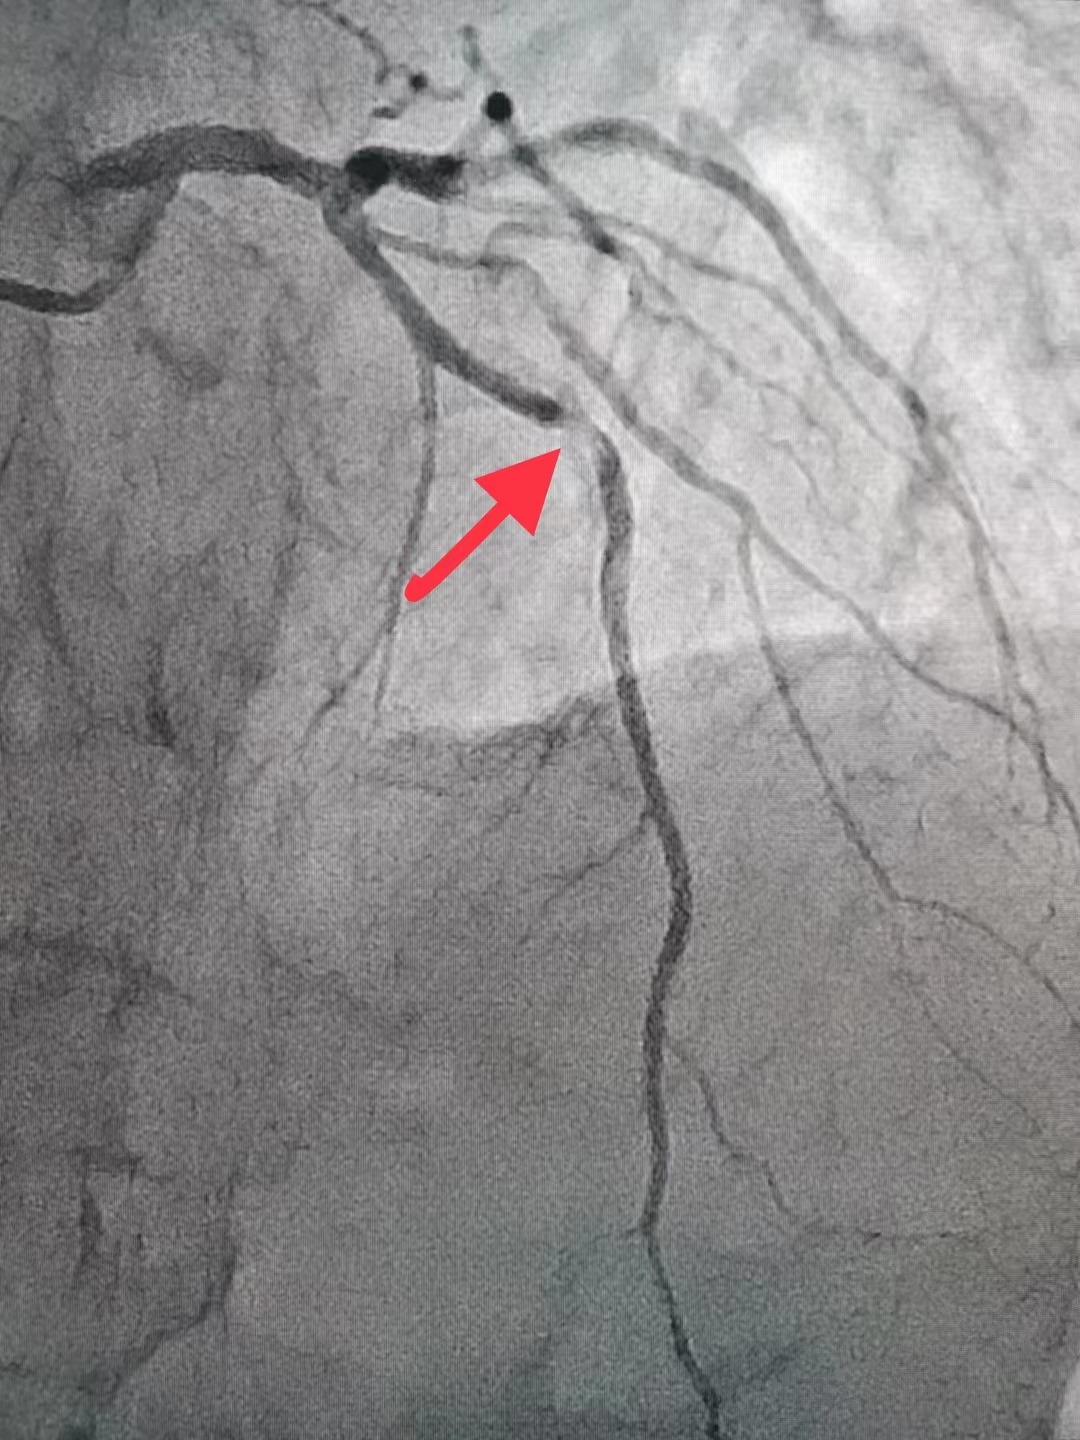

冠脉造影结果:LM外膜钙化,内膜不光滑,中段狭窄90%,TIMI3级。LCX外膜钙化,内膜不光滑,TIMI3级。RCA外膜钙化,内膜不光滑,近段狭窄80%,中段狭窄90%,可见破损斑块,TIMI3级。

冠脉内介入治疗